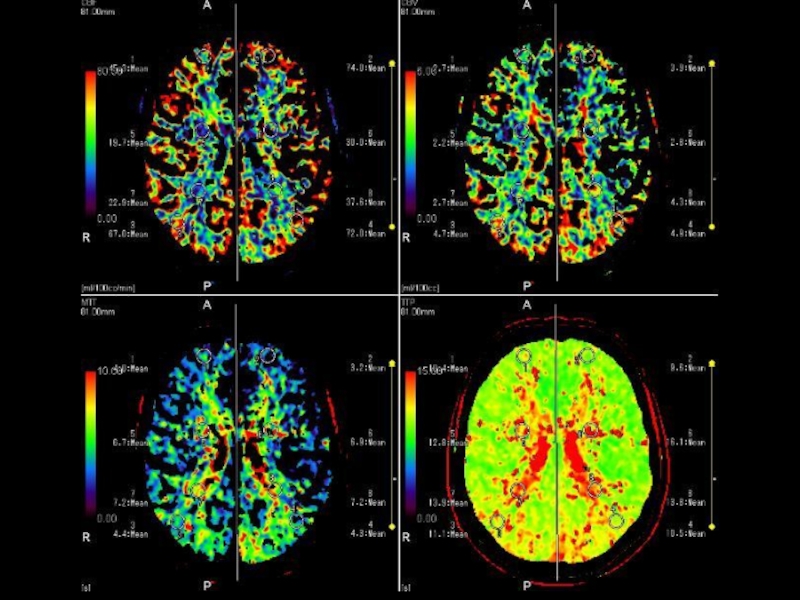

ADS-MAPS